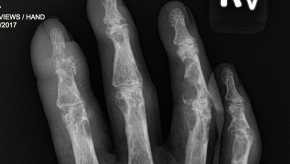

Reduction on radiographic progression has now become the standard of care in the therapies used to treat psoriatic arthritis and, during the 2017 ACR Meeting, several agents reported the results of their studies with radiographic endpoints.